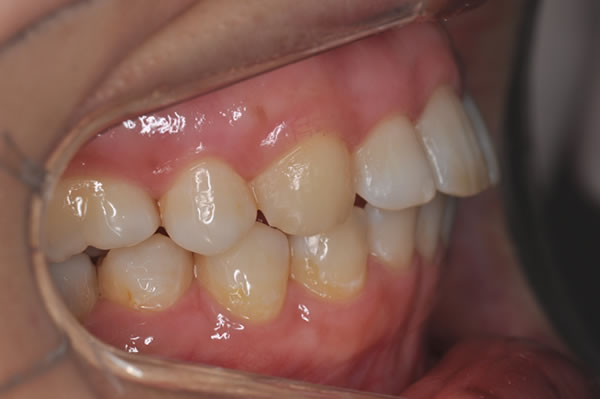

上顎前突症の治療例

上顎前突症(出っ歯)の矯正症例 ケース01

| 治療前(初診) | 治療後 | |